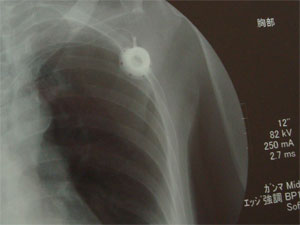

こちら、また胸の中のひまわりです。